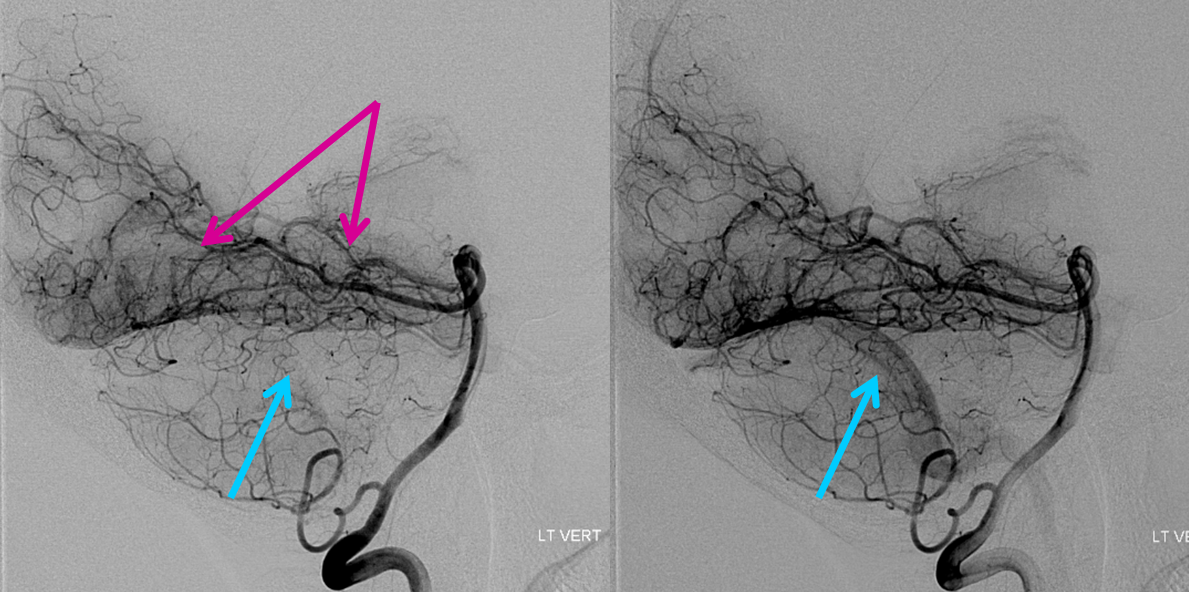

3D from the right, showing left-sided PED in place. Notice extra bums on the aneurysm

Accessing the left A2 proved to be the hardest task due to the tortuosity of the vessels. Finally, an Avigo went through distally enough to allow the Phenom to come off the aneurysm where its edge was being caught.

After placement of the Phenom, confirming patency of vessels and other lack of injury. I would recommend doing this after complicated maneuvers. If there is a problem you have a choice to stop.